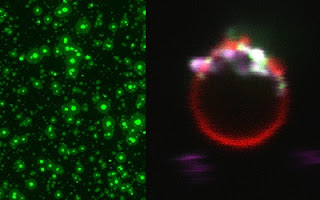

Convierten células de piel en neuronas para estudiar la epilepsia

El logro de científicos del CONICET, del Instituto Leloir, del Hospital J. M. Ramos Mejía y de la Universidad Austral es con fines de investigación, para estudiar una enfermedad neurológica y testear posibles tratamientos. Las muestras se tomaron de dos pacientes con epilepsia y dos familiares cercanos.

Por primera vez un grupo de científicos argentinos empleó una tecnología llamada “reprogramación celular” para generar neuronas para el estudio de una enfermedad neurológica, en este caso, cierto tipo de epilepsia.